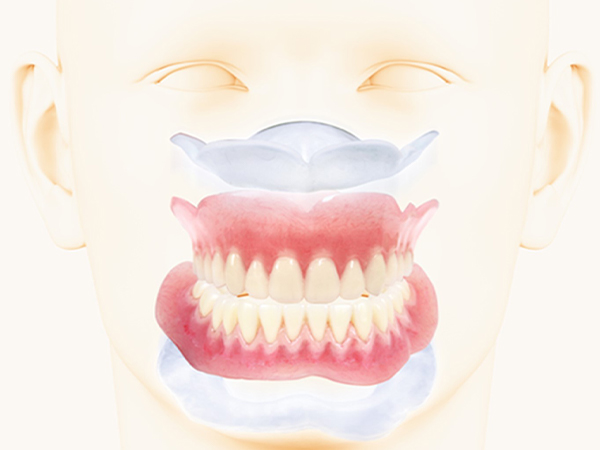

入れ歯(義歯)とは

入れ歯とは、人工の歯を用いた取り外し可能な装置で、歯を失った部分を補う治療法になります。

入れ歯は、失った歯の数により「総入れ歯」と「部分入れ歯」に大きく分けられます。

歯を全て失った場合は、「総入れ歯」となります。保険の総入れ歯はレジンというプラスチックの材料からできた床(ピンクの部分)と人工歯からできています。